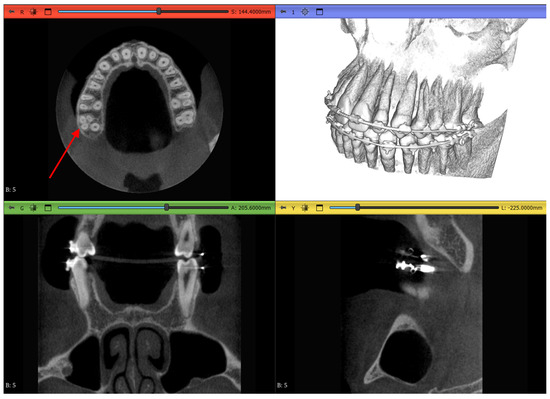

2.3.1. Volume Cropping

2.3.2. Histogram Adjustment

2.3.3. Thresholding Masking